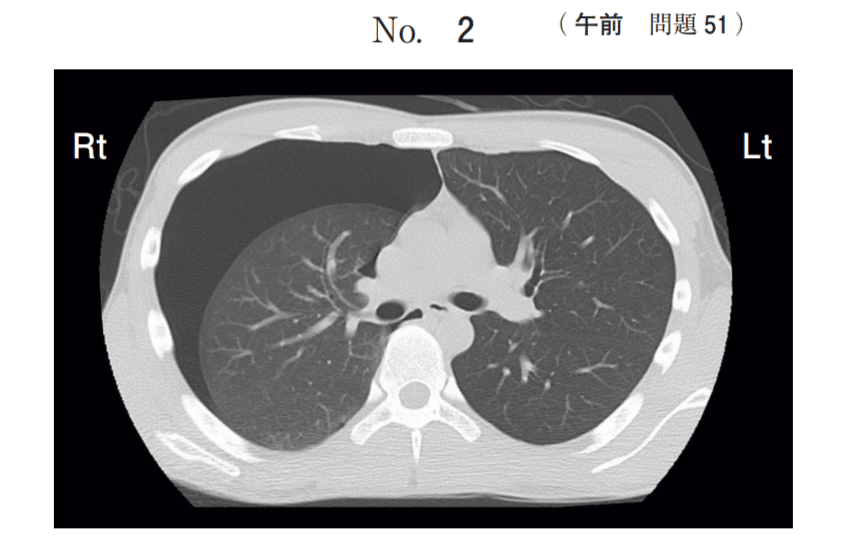

【問51】Aさん(27歳、男性)は、突然の胸痛と呼吸困難があり、救急外来を受診した。意識は清明。身長179cm、体重63kg、胸郭は扁平である。20歳から1日50本の喫煙をしている。バイタルサインは、体温36.1℃、呼吸数22/分、経皮的動脈血酸素飽和度(SpO₂)96%(room air)である。

胸部CT(別冊No. 2)を示す。

(出典:厚生労働省 第114回看護師国家試験 午前問題 問51 別冊No.2)

長身痩せ型の若年男性、喫煙歴、突然の胸痛・呼吸困難というキーワードと胸部CT画像で右肺が虚脱している所見から診断は「右自然気胸」です。肺が虚脱しているため、その部位の呼吸音は聴こえにくく(減弱)なります。

右肺野の呼吸音は減弱している。: 正解。 CT画像で右肺が虚脱し、胸腔内に空気が溜まっていることがわかります。虚脱した肺には空気が入らないため聴診すると右肺野の呼吸音は著しく減弱または消失します。

左胸腔内は液体成分で占められている。: 不正解。CT画像で異常があるのは「右」胸腔であり、溜まっているのは液体(白っぽく写る)ではなく空気(黒く写る)です。

自然気胸: 明らかな原因なく肺に穴が開き、空気が漏れて肺が虚脱する疾患です。長身痩せ型(ブラ形成が原因)の若年男性に好発します。

緊張性気胸: 漏れた空気が胸腔内にパンパンに溜まり心臓や健側の肺を圧迫する重篤な状態です。CT画像では、縦隔(心臓や気管)が健側(左側)に圧排されている所見がみられ緊急の胸腔ドレナージが必要です。